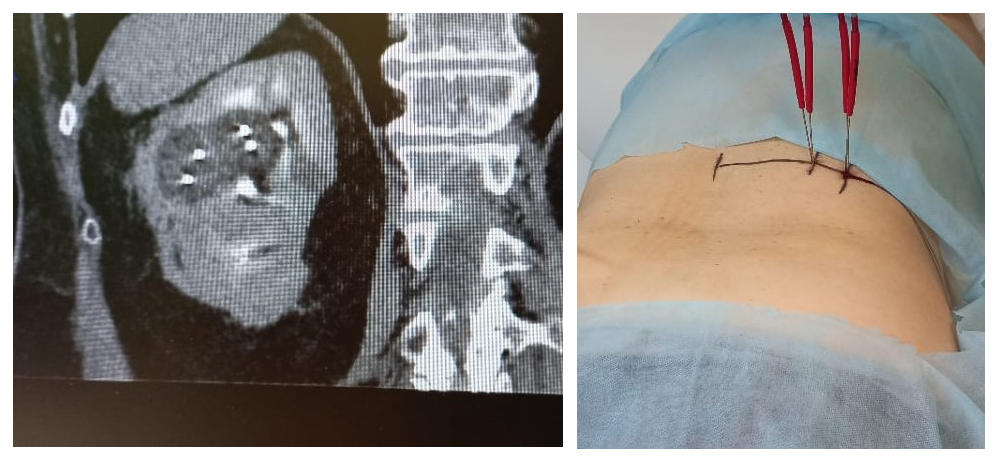

Рисунок 5 - Криоаблация двух рядом расположенных опухолей

Рисунок 6 - Пример гидродиссекции при близком прилежании угла двенадцатиперстной кишки у больного с опухолью единственной почки